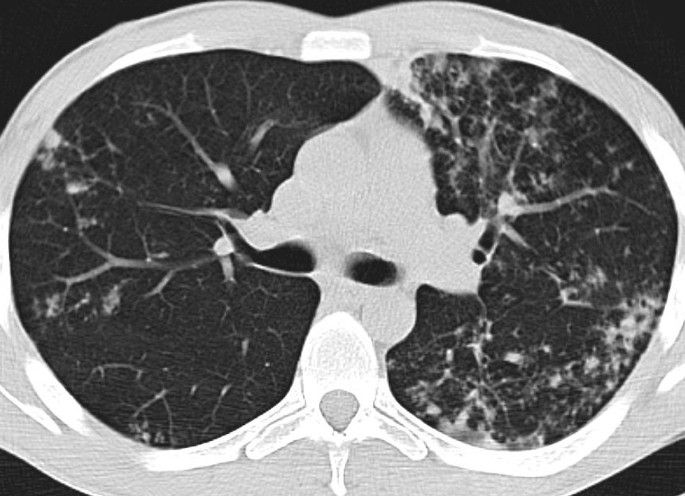

Визуализация и диагностика неинвазивного аспергиллеза с помощью КТ

Раздел: Необычные решения